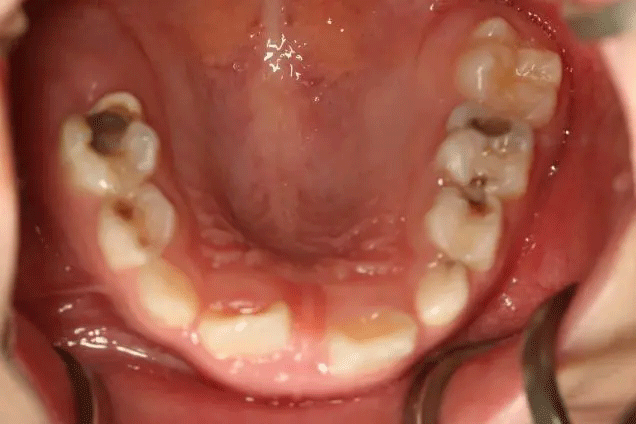

孩子1歲開始已經(jīng)出現(xiàn)齲齒

但是媽媽2年后才帶孩子就診

這時(shí),孩子已經(jīng)斷斷續(xù)續(xù)疼了3年

來口腔科檢查的孩子

有些牙齒都已經(jīng)爛得很嚴(yán)重了

甚至牙齒幾乎都爛光僅剩下牙根

孩子不喊疼,家長很少會(huì)帶來看牙